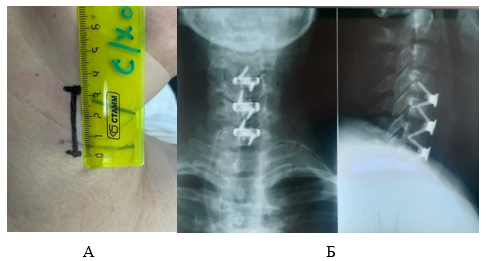

Разметка кожного разреза выполнялась при помощи рентгеноскопического оборудования. Необходимые анатомические структуры обозначены в виде пунктирных линий на коже (рис. 2А).

Рис. 2. Разметка кожного разреза для авторского доступа и по Smith – Robinson: 2А - разметка кожного разреза; 2Б - сравнение кожных разрезов по Smith – Robinson (пунктирная линия) и авторского паратрахеального (сплошная линия); 2В - этап вскрытия глубокой фасции шеи (1 – висцеральный листок, 2 - m. sternohyoideus)

Источник: составлено авторами

Проекция межпозвоночного диска, требующего оперативного лечения, изображена поперечной сплошной линией серого цвета, а медиальный край m. sternocleidomastoideus отображен в виде пунктирной линии фиолетового цвета. Край трахеи помечен пунктирной линией оранжевого цвета. Кожный разрез располагался на 2 мм медиальнее наружного края трахеи и показан черной сплошной линией. Сам разрез не превышал 2 см при одноуровневой дискэктомии (рис. 2Б). Для сравнения на рисунке 2Б пунктирной линией изображен кожный разрез для доступа по Smith – Robinson. После кожного разреза рассекали и «тупо» разводили в стороны подкожно-жировую клетчатку, вскрывали поверхностную фасцию шеи. Далее вдоль линии разреза платизмы вскрывали глубокую под подъязычную (предтрахеальную) фасцию шеи (рис. 2В), «тупо» выделяли переднюю поверхность позвоночника, а m. sternohyoideus на верхних уровнях и m. sternothyroideus в нижних отделах смещали латерально. После вскрытия превертебральной фасции и передней продольной связки возможны любые манипуляции на шейном отделе позвоночника. В зависимости от операционной ситуации разрез можно расширить как краниально, так и каудально без риска травмы сосудов и нервов и внешнего вида в отличие от поперечного разреза по Cloward (рис. 3).

Рис. 3. Полисегментарная дискэктомия: 3А - разметки паратрахеального доступа при полисегментарной дискэтомии; 3Б - контрольные рентгенограммы после операции